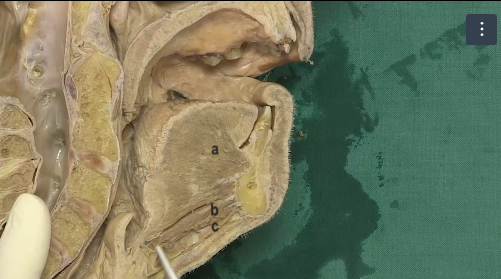

a,b,c,d

A

a: stylohyoid muscle

b: posterior belly of digastric

c: anterior belly of digastric

d: intermediate tendon